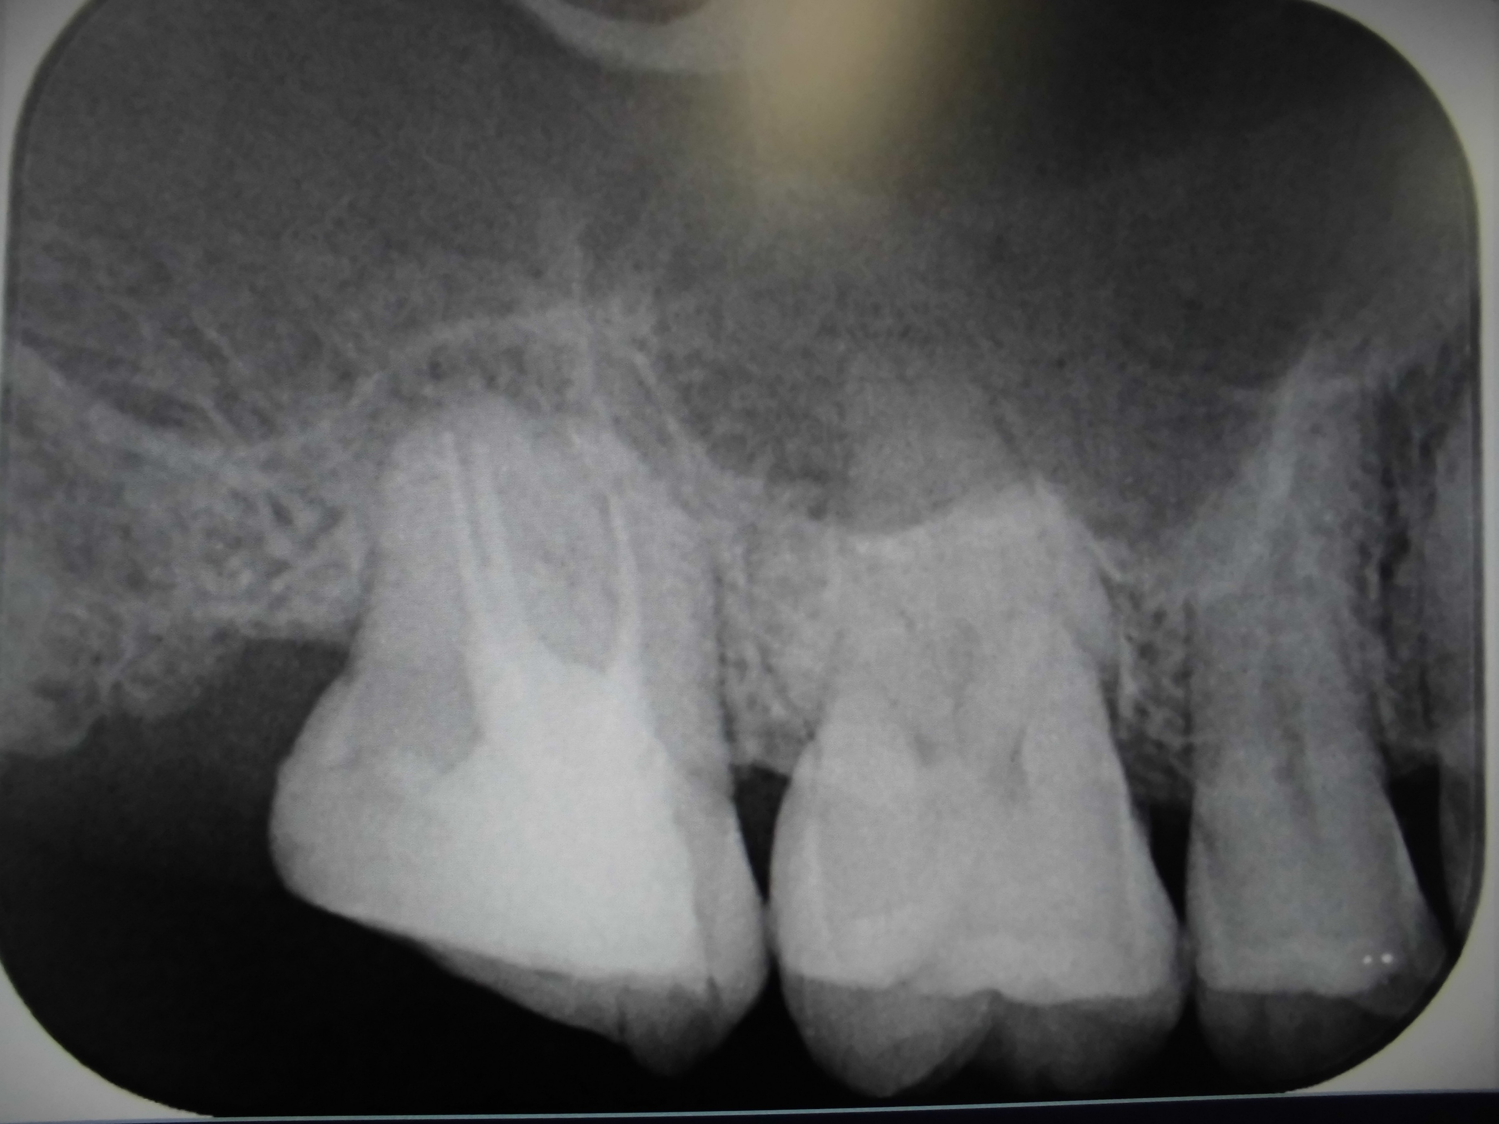

当院では令和7年9月より歯科用CT(コンピュータ断層撮影)を導入しました。

それにより、診療に大きなメリットがありますので、積極的に活用させていただきます。

歯科用CTの被ばく量は医科用頭部CTに比べてかなり低いです。

ただし、通常の歯科X線よりは大きいです。

「歯科用CTは医科用の頭部CTより10分の1程度の被ばく量です。ただし普通のレントゲンよりは多いので、必要な場合に限って撮影します」